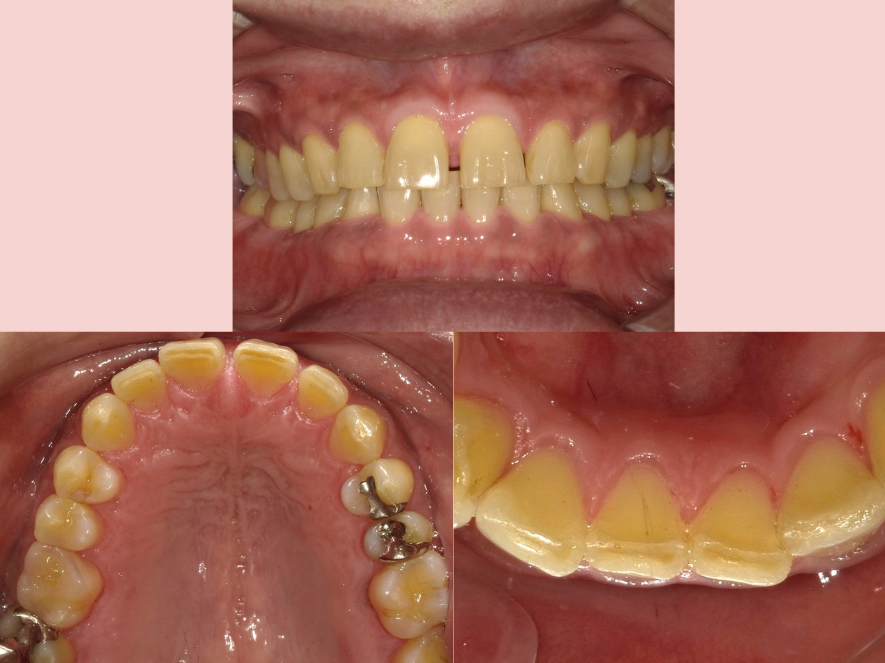

治療後

| 治療名称 | エアフロー+PMTC |

|---|---|

| 年齢・性別 | 50代・男性 |

| 主訴 | メンテナンス前に着色を落として綺麗にしたい。 |

| 期間 | 1回 |

| 費用 | 5.500円 |